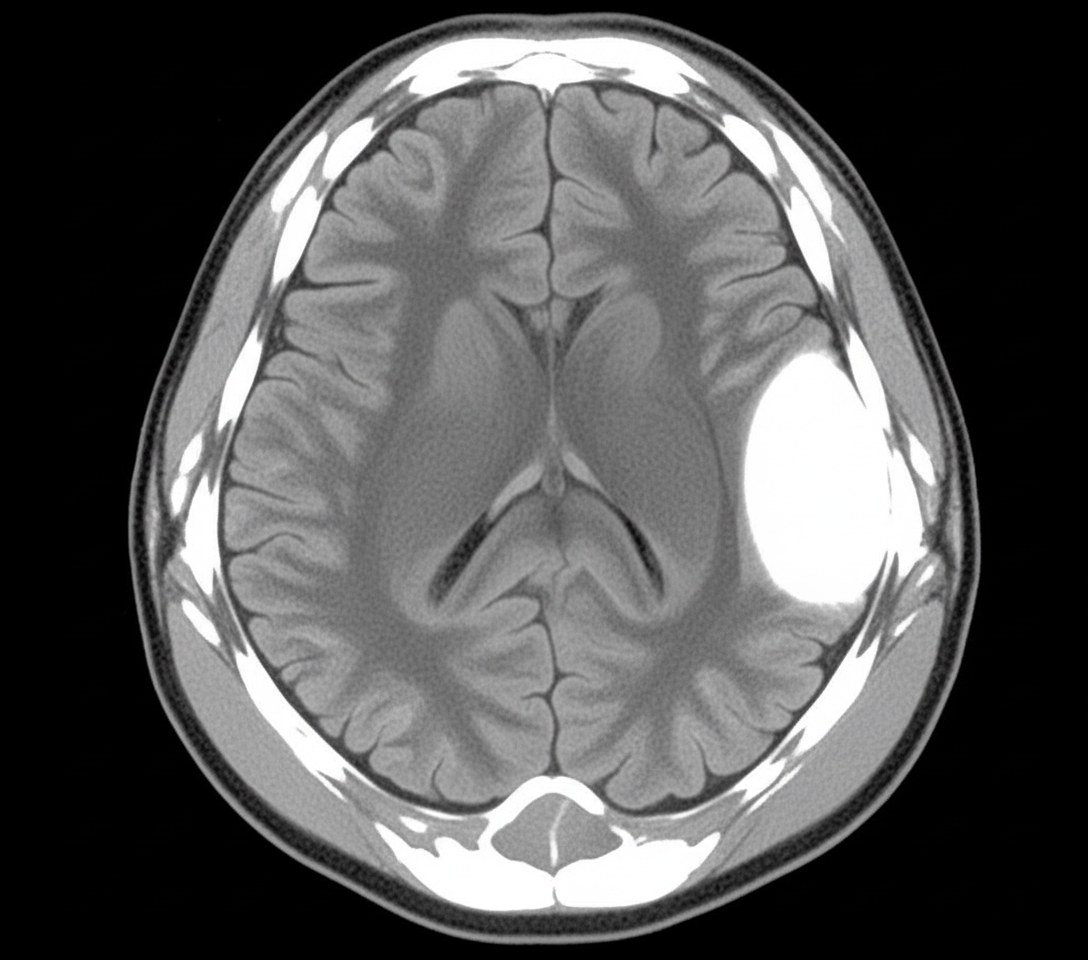

A 20-year-old male presented to the ER with altered sensorium, short-term memory loss, and severe headache after a road traffic accident. There was evidence of skull injury. A non-contrast CT head was performed. The artery most commonly involved in the above condition passes through which of the following structures?

Explanation: ***Pterion*** - The clinical presentation suggests an **epidural hematoma** following skull fracture, most commonly caused by rupture of the **middle meningeal artery (MMA)**. - The MMA runs deep to the **pterion**, which is the thinnest part of the skull and most vulnerable to fracture in head trauma, producing the classic **biconvex (lens-shaped)** appearance on CT. *Anterior clinoid process* - This bony projection is related to the **internal carotid artery** and **optic nerve**, not the middle meningeal artery. - Injury here would more likely cause **visual disturbances** or **carotid-cavernous fistula**, not the typical epidural hematoma pattern. *Foramen ovale* - This foramen transmits the **mandibular division of trigeminal nerve (CN V3)** and **accessory meningeal artery**. - Damage here would cause **trigeminal nerve dysfunction** with jaw weakness and sensory loss, not epidural bleeding. *Carotid canal* - This canal transmits the **internal carotid artery** through the temporal bone into the middle cranial fossa. - Injury would result in **massive hemorrhage** or **stroke symptoms**, not the localized epidural hematoma described.